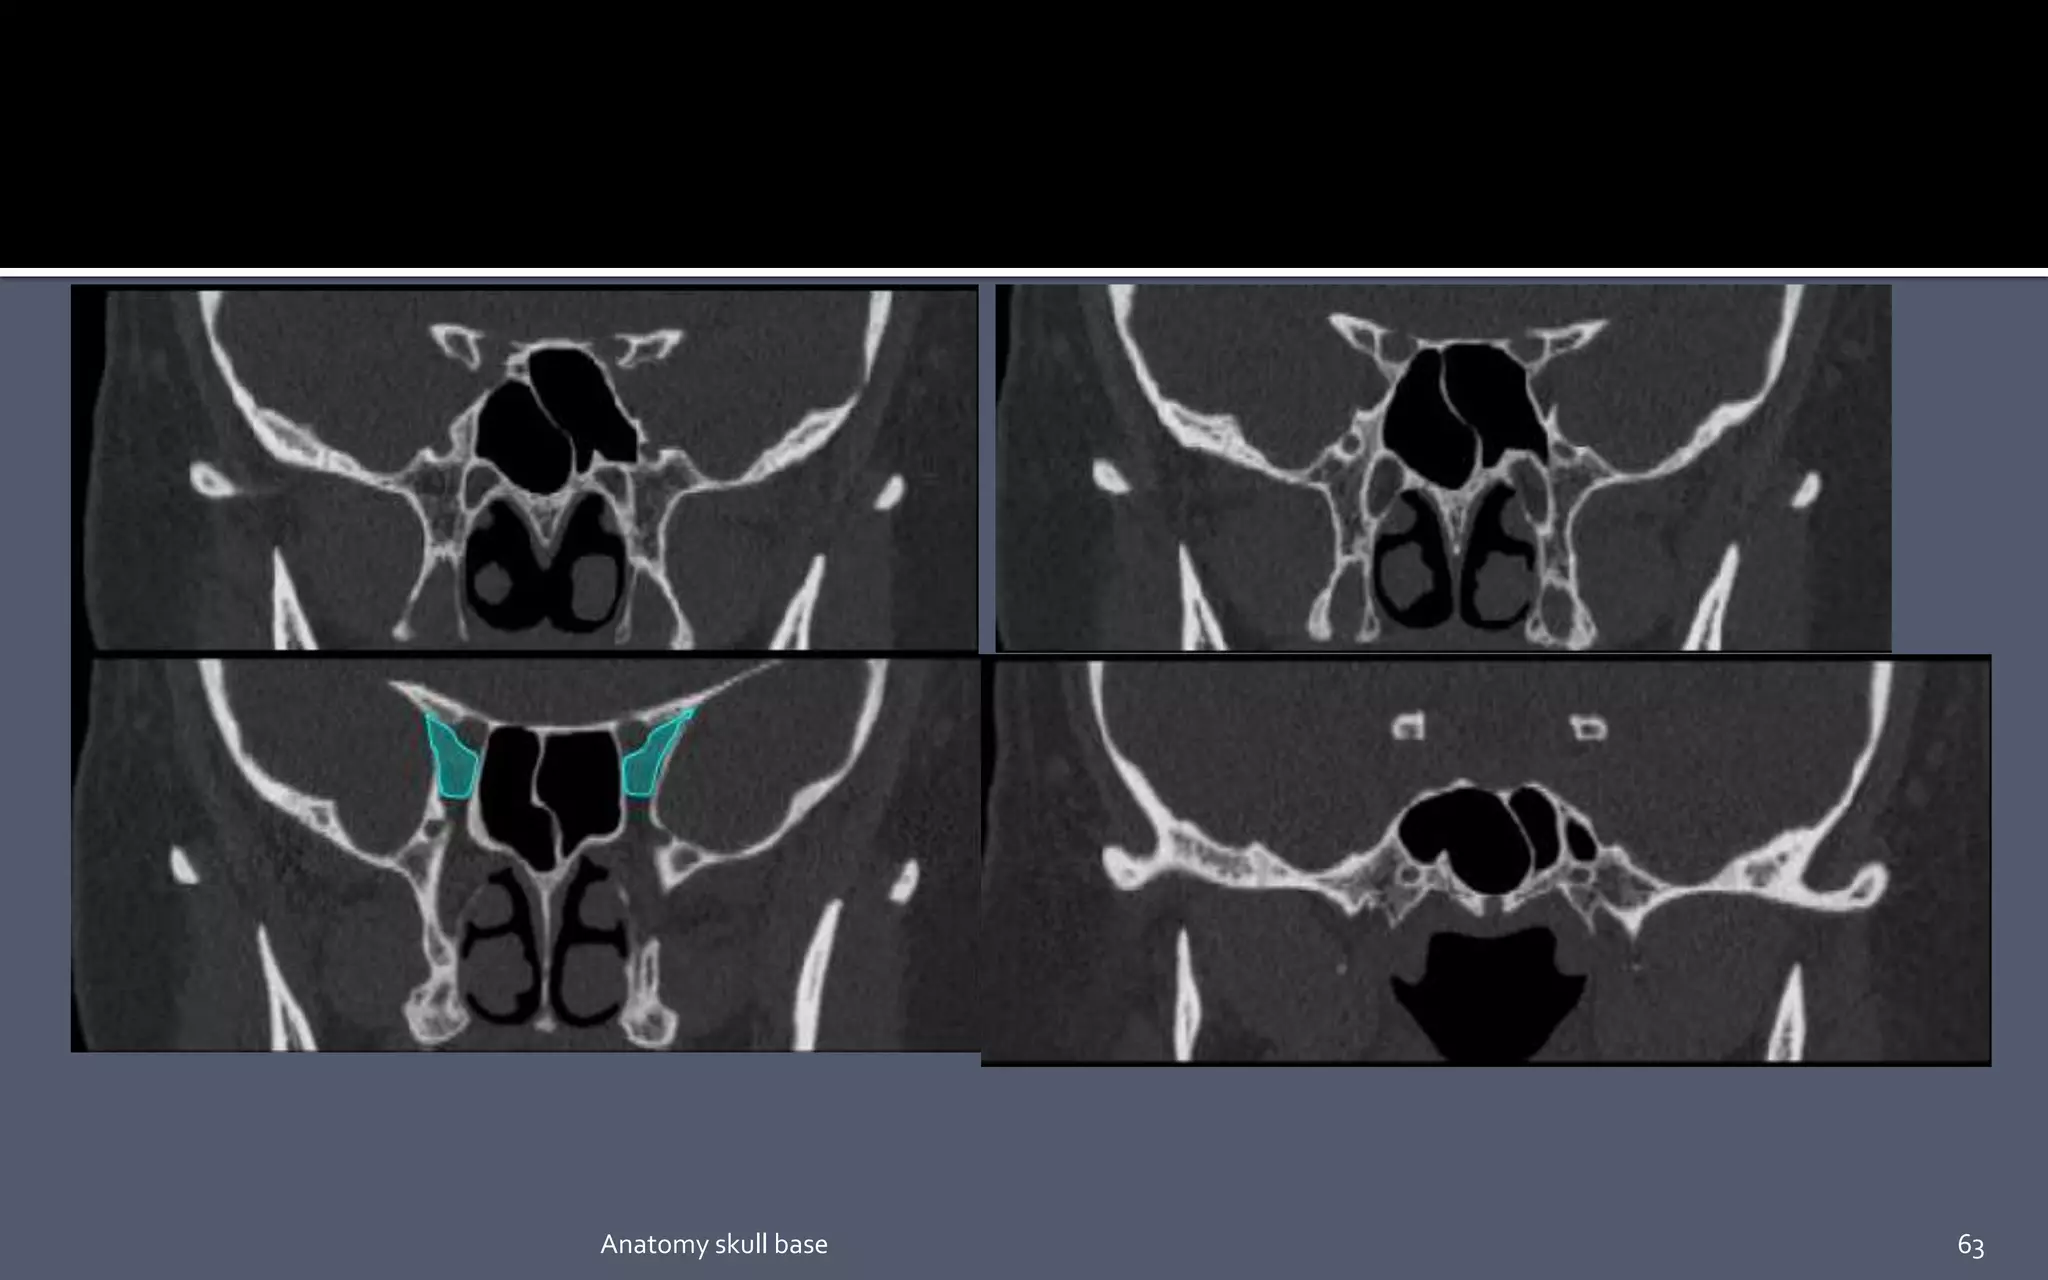

 Crista galli :- (latin for cock’s comb) Provides the site for anterior most

attachment of the falx cerebri.

 Cribriform plate :- It is a sheet of bone which contains numerous small

foramina – these transmit olfactory nerve fibres (CN I) into the nasal cavity.

 Anterior ethmoidal foramen transmits the anterior ethmoidal artery, nerve and vein.

 Posterior ethmoidal foramen transmits the posterior ethmoidal artery, nerve and vein.